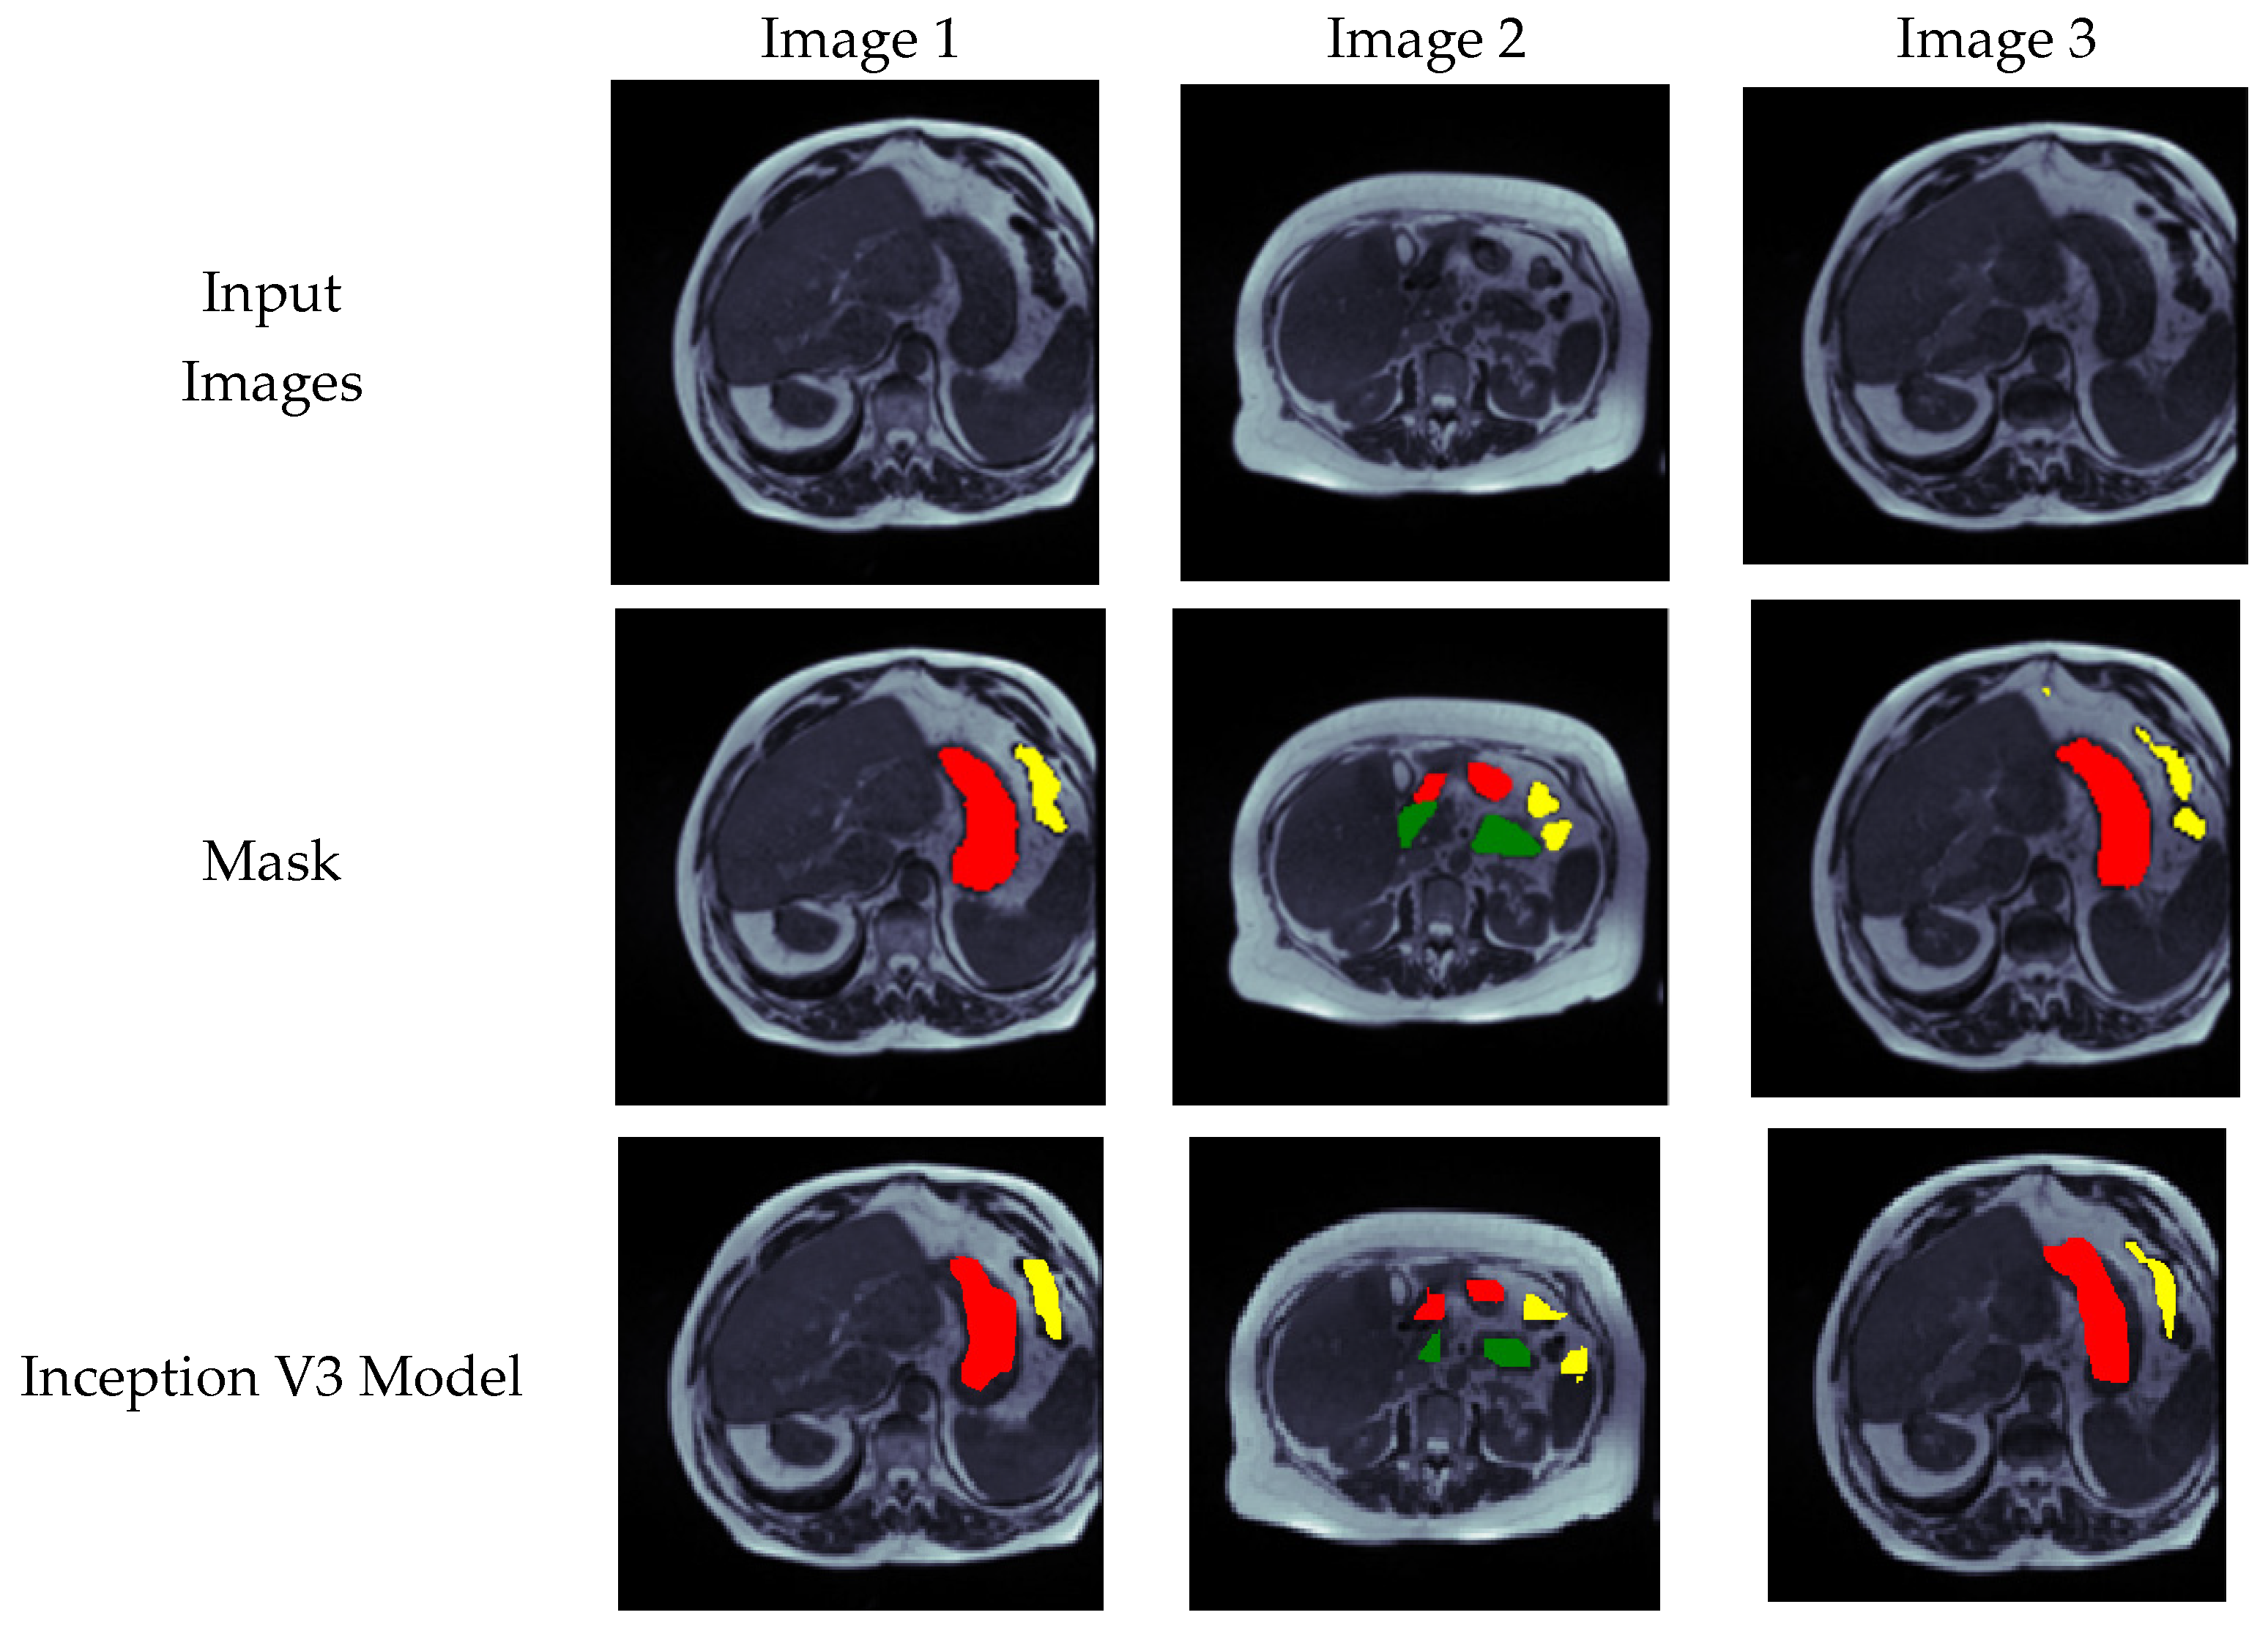

4.5. Visual Analysis of Segmented Images